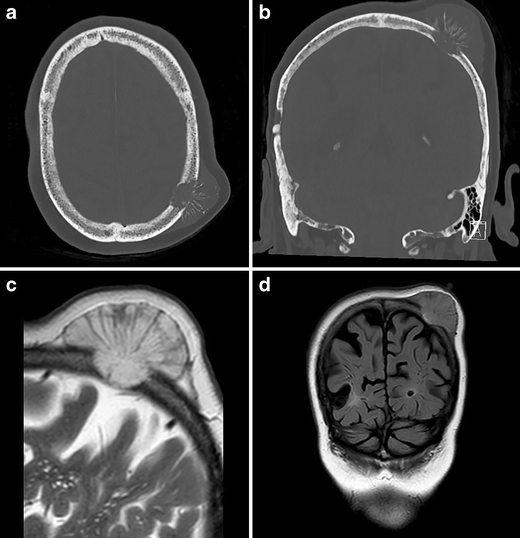

a Transverse and b coronal CT, windowed to bone setting, demonstrating destruction of both the external and internal tabula of the skull. Extracranial radial striped calcified fragments are present. c Sagittal T2-weighted and d coronal FLAIR MRI, demonstrating growth to the level of the dura mater, without parenchymal involvement